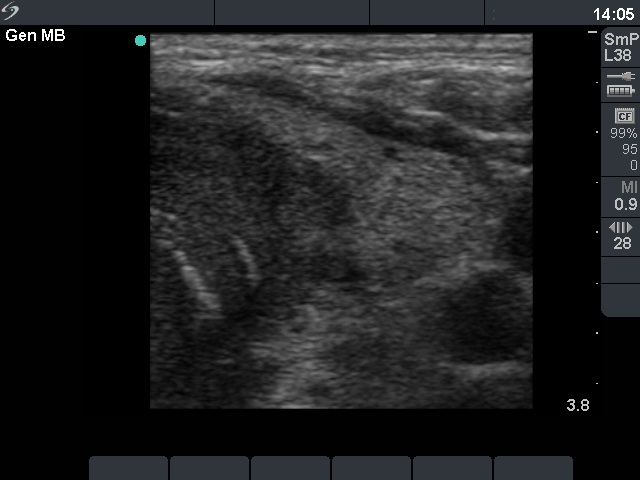

Ultrasonography: the right lobe was intact. On the dorsal part of the left lobe there was hypoechogenic mass spreading to the dorsal part of the isthmus. There was no blood flow within the nodule on color Doppler.

The US pattern is very specific for cancer. Such macroscopic proof of an invasively spreading cancer is rarely seen. The lack of enlarged lymph nodes in the neck would be a very unusual finding in the event of such an aggressive form of a papillary or medullary cancer. This property itself raises the possibility that the thyroid carcinoma is not a primary one.